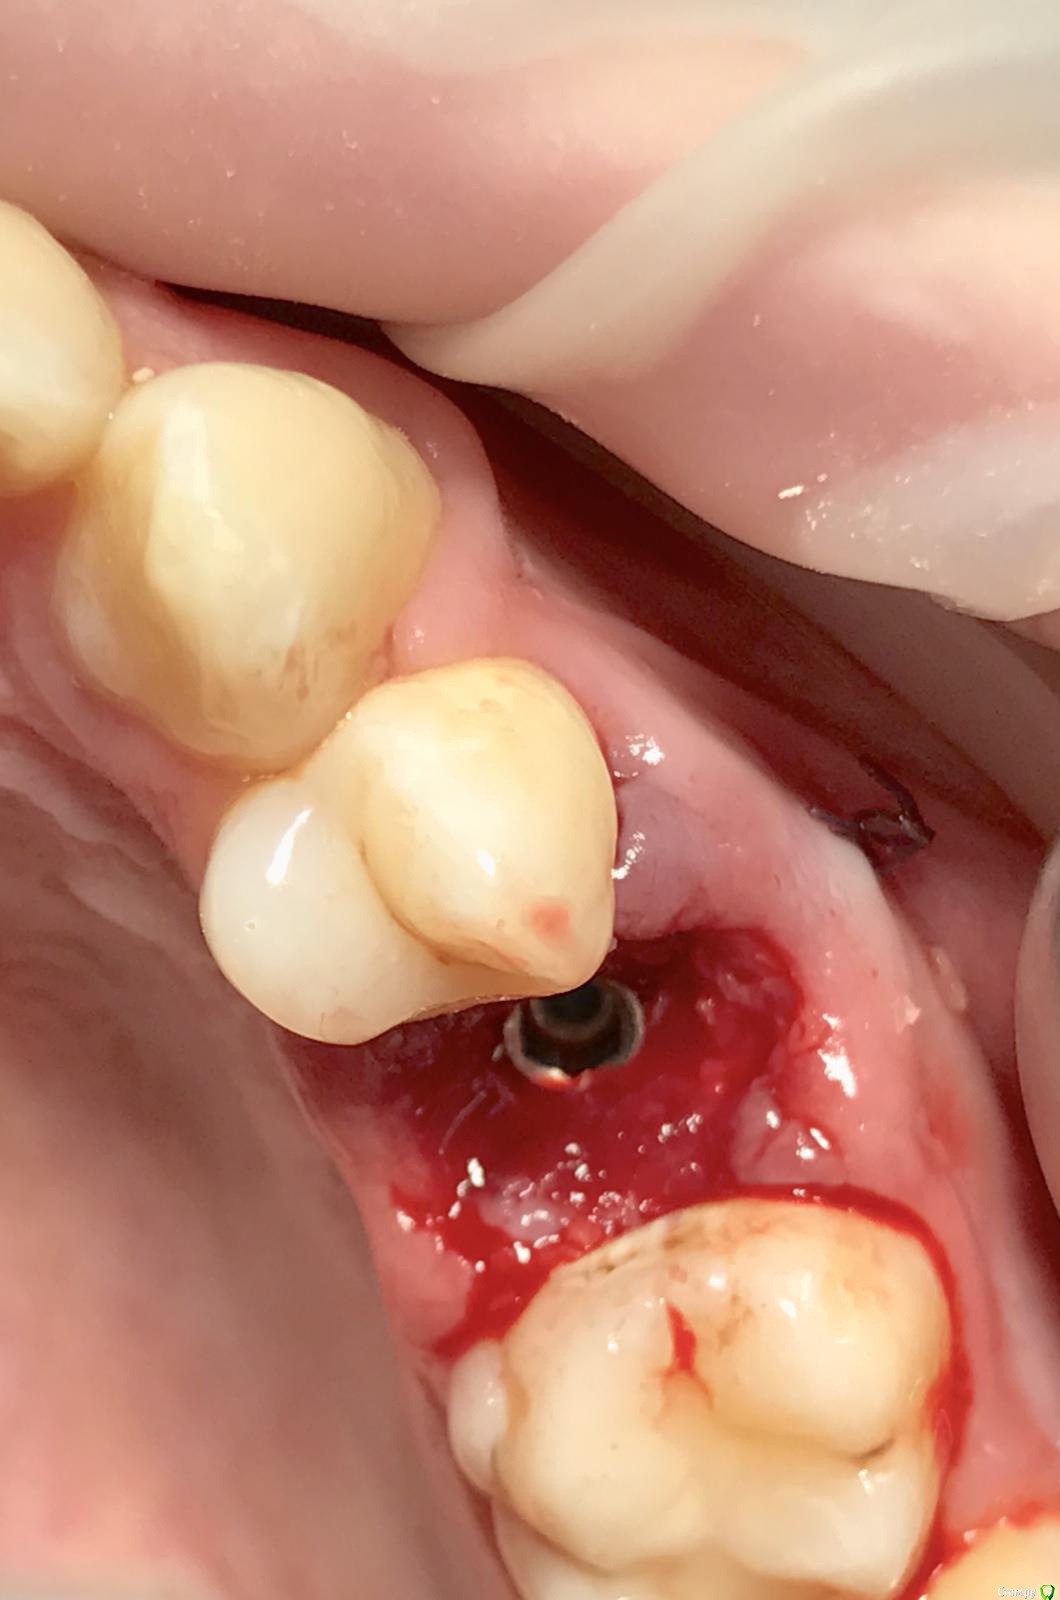

Ponchik Опубликовано 15 июня, 2017 Поделиться Опубликовано 15 июня, 2017 Планируется удаление 22 с одномоментной имплантацией Алфа-био (Nice).Опыт хирургический небольшой. Ортопедического нет совсем. Четыре десятка имплантатов за всю жизнь и только двухэтапно. Зуб удаляется по поводу перелома корня (вкладкой) Воспалительные явления не глубоко надеюсь хорошо отмыть (хлоргексидин, потом физраствор) и отскоблить под контролем скопа.Установить nice и если торк позволит поставить временный абатмент и на него слепить композитную коронку либо старую коронку. Вопросы:1. Не рисковать и делать двухэтапно (с нкр) Временно сделать "бабочку"2. Если нагружать сразу, то какой временный абатмент взять? Может кто работает этой системой? На месте подсказать не кому. Ортопед про имплантат слышать не хочет. Только мост. Пациент мой ассистент. Надеется, что малое количество опыта компенсируется старанием ) Ссылка на комментарий

Ponchik Опубликовано 16 июня, 2017 Автор Поделиться Опубликовано 16 июня, 2017 Спасибо за советы. Размерность - альфа-био Nice 3.2 - 13 мм - этот вариант на КТ. Можно взять 16мм Ссылка на комментарий